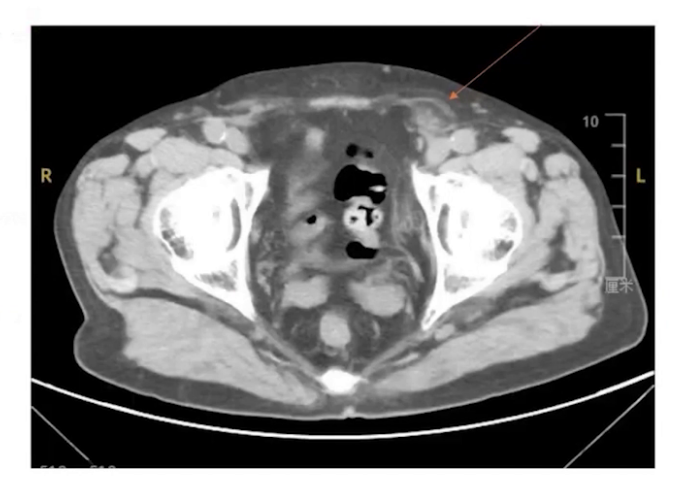

(3)影像学检查:腹部B超提示左侧腹股沟区肿块与腹腔相通,为左侧腹股沟疝;腹部平扫CT显示左侧腹股沟区突出的疝块,且疝块不大。